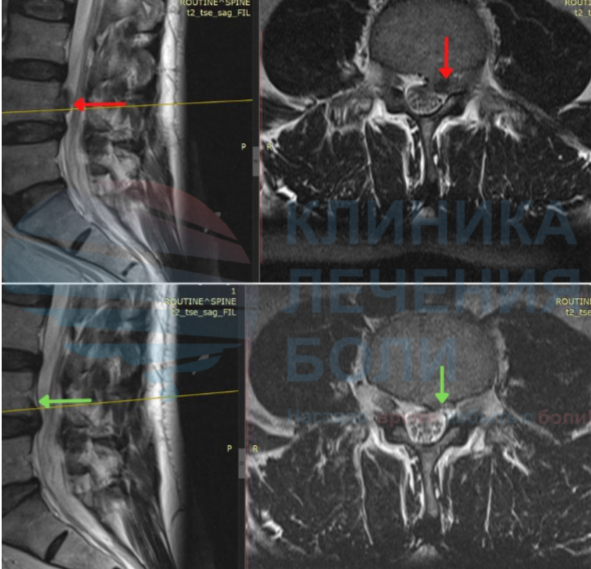

Повышаем вероятность уменьшения или исчезновения грыжи до 94% с помощью метода модулируемой резорбции

Эта методика была предложена талантливыми врачами А.М.Ткачевым и А.В. Епифановым, длительное время изучавшими эти процессы. Суть метода состоит в воздействии лазером средней интенсивности на зону, находящуюся в проекции грыжи в течении 20 минут на протяжении 14 дней. Лазеротерапия приводит нескольким важным эффектам:

По статистическим результатам разница в скорости восстановления при Спонтанной и Модулируемой резорбции составляет от 5 до 10 месяцев. Метод достоверно уменьшает сроки нетрудоспособности, позволяет быстро купировать болевой синдром, увеличить подвижность и быстрее вернуться к рабочему графику.

Мы первый в Тюменской области центр, который занимается резорбцией грыжи диска (методом безоперационного уменьшение или полного рассасывание грыжи). Благодаря нашему правильному подходу сотни пациентов избежали операций по удалению грыжи диска.